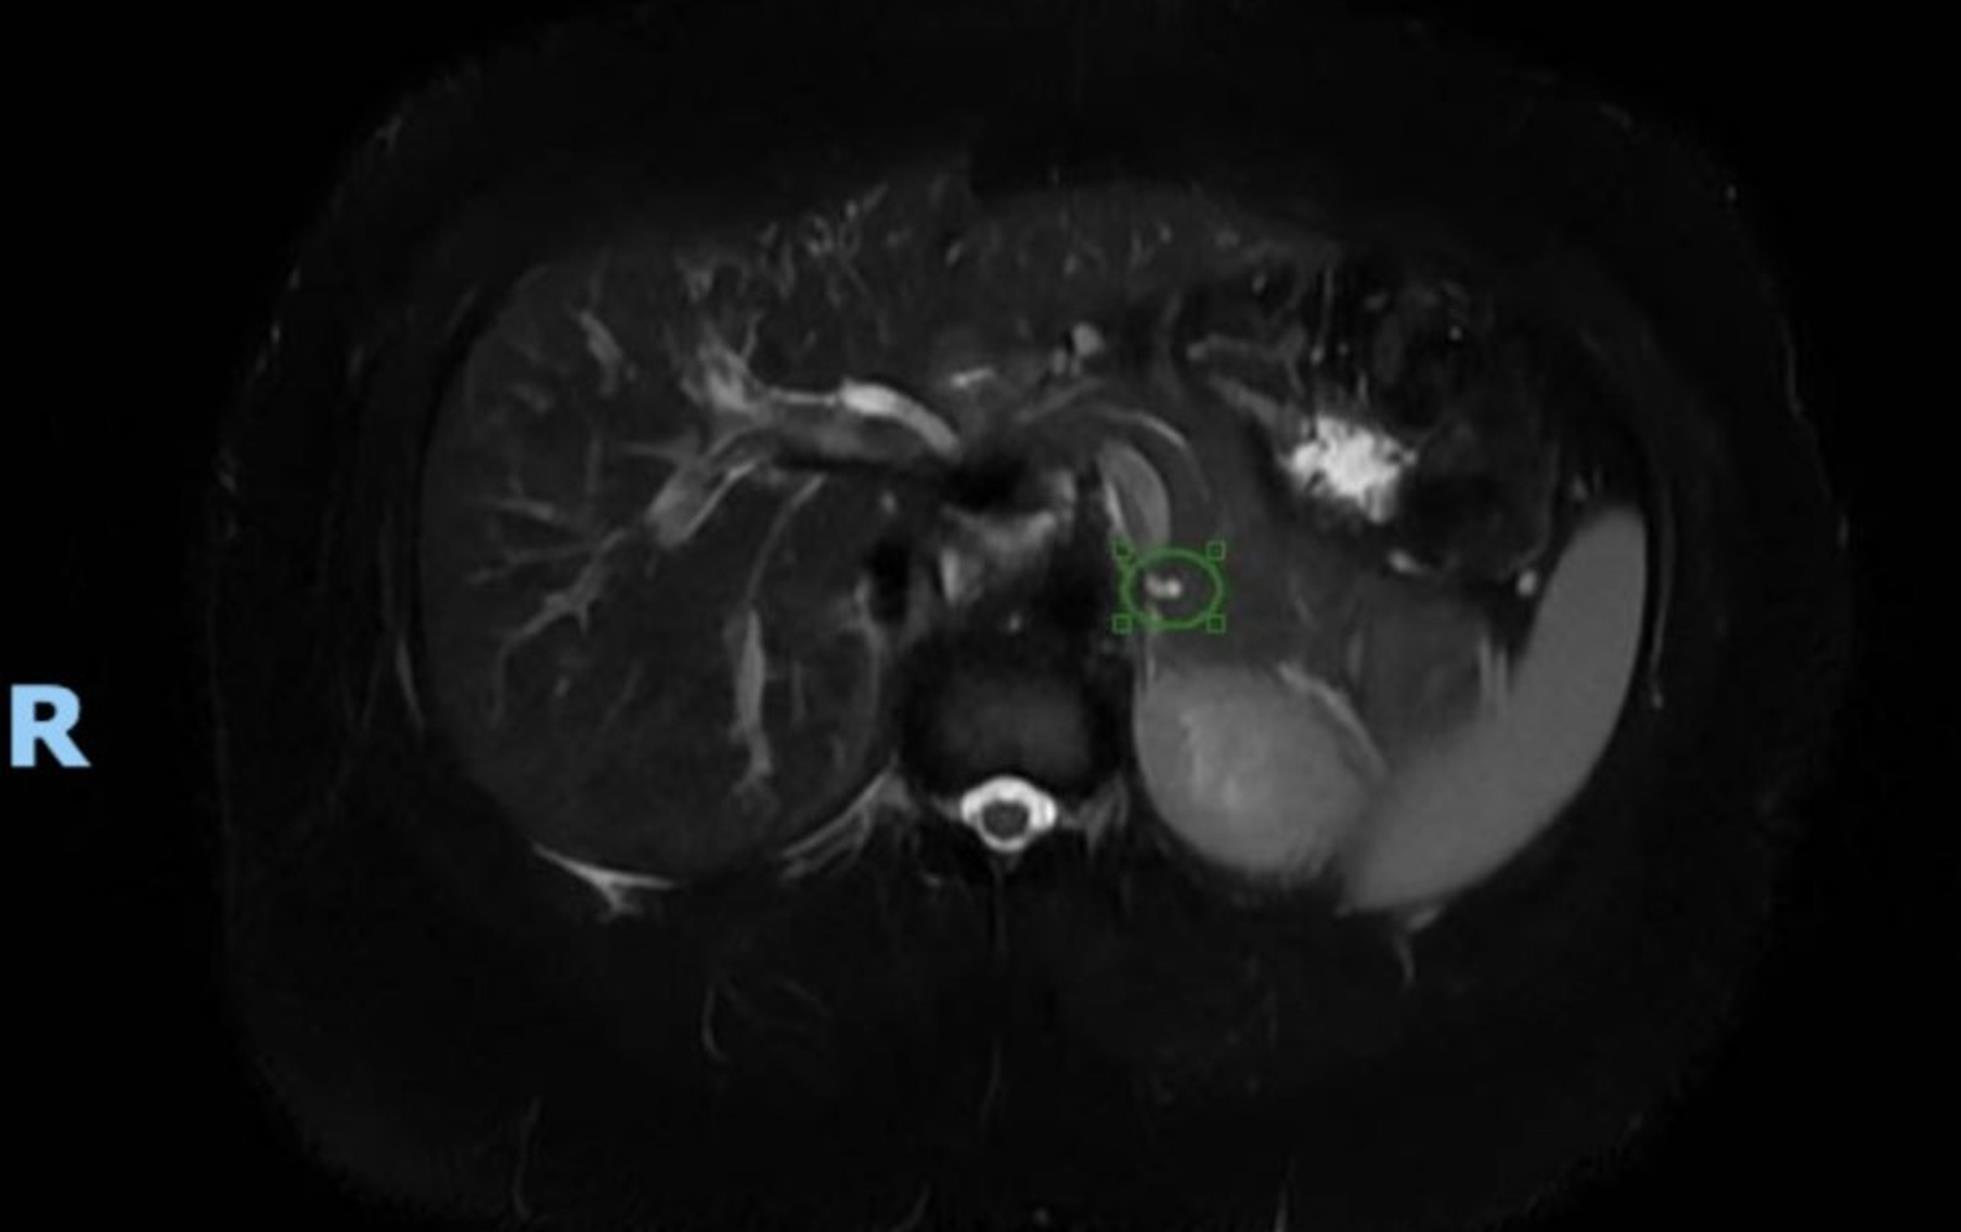

A 32-year-old female with a past medical history significant for asthma, goiter, irritable bowel syndrome, a laparoscopic cholecystectomy in 2020, and a laparoscopic appendectomy in 2022 presented to the emergency room in April 2024 with a severe episode of epigastric pain that had been occurring intermittently over the past several months. CT Abdomen/Pelvis completed on presentation showed a 19 mm cystic focus within the pancreatic tail. An MRI with MRCP, both with and without IV contrast, revealed a cystic lesion in the pancreatic tail measuring up to 2.0 × 1.9 cm. The lesion was characterized by thin peripheral enhancement, with no discernible nodularity, solid mass, or pancreatic ductal dilatation (Fig. 1). This was a significant increase in size from a previous MRI finding in February 2022, which showed dimensions of 0.6 × 0.3 cm (Fig. 2). The patient was further evaluated via EUS with fine needle aspiration (FNA) biopsy. Endosonographic findings confirmed those on MRI and CT, revealing an anechoic lesion measuring 17 mm × 16 mm in maximal cross-sectional diameter with two thinly septated compartments near the junction of the pancreatic tail. There was no associated mass or internal debris within the fluid-filled cavity. Analysis of the components from FNA was non-diagnostic due to scant cellular material, few inflammatory cells, and amorphous material. The overall findings on EUS and FNA were consistent with the MCN of the pancreas. After the endoscopy, the patient underwent an uncomplicated intraoperative resection via robotic spleen-sparing distal pancreatectomy in June 2024. Surgical pathology confirmed a benign MCN with low-grade mucinous epithelium and an ovarian-type stroma, which showed strong diffuse immunoreactivity for CD10 and the progesterone receptor. Gross pathology revealed a 2.1 × 1.1 × 1.0 cm tan-white smooth-lined, clear fluid-filled cyst that had no involvement with the pancreatic duct.

MRI showing significantly increased pancreatic cyst in 2024.

Fig. 1  MRI showing significantly increased pancreatic cyst in 2024.

An MRI with MRCP with and without IV contrast revealed a cystic lesion in the pancreatic tail that measured up to 2.0 × 1.9 cm and that was characterized by thin peripheral enhancement without any discernible nodularity, solid mass, or pancreatic ductal dilatation.